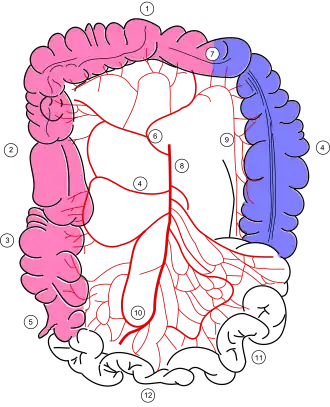

Colonic blood supply

The colon receives blood from both the superior and inferior mesenteric arteries. The blood supply from these two major arteries overlaps, with abundant collateral circulation via the marginal artery of the colon. However, there are weak points, or "watershed" areas, at the borders of the territory supplied by each of these arteries, such as the splenic flexure and the rectosigmoid junction. These watershed areas are most vulnerable to ischemia when blood flow decreases, as they have the fewest vascular collaterals.

The rectum receives blood from both the inferior mesenteric artery and the internal iliac artery; the rectum is rarely involved by colonic ischemia due to this dual blood supply.